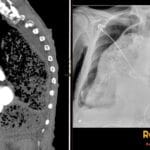

- Radiology Cases: Images with a to-the-point discussion highlighting the specific diagnostic criteria.

Latest Radiology Cases